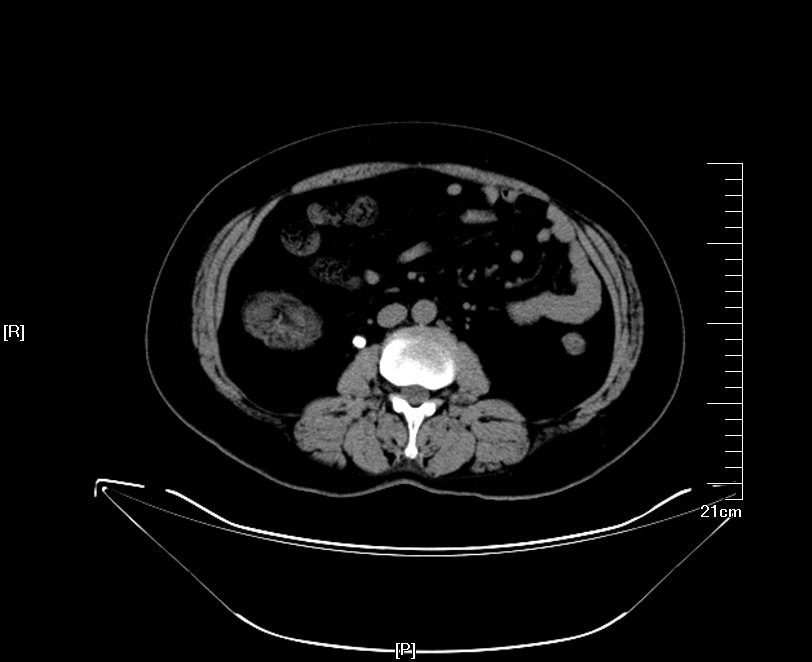

体外冲击波碎石术注意事项 体外冲击波碎石,是一种特别有效的泌尿结石治疗方案。通过体外的冲击能量,传递到肾脏、输尿管,使结石粉碎。治疗以后要观察是否存在肾脏损伤

体外冲击波碎石手术时有一些禁忌和注意事项 , 因此要注意 : 一、适应症与禁忌症 理论上来说 , 除无法纠正的出血性疾病及结石远端的腔道梗阻为体外碎石的 绝对禁忌症外 , 其